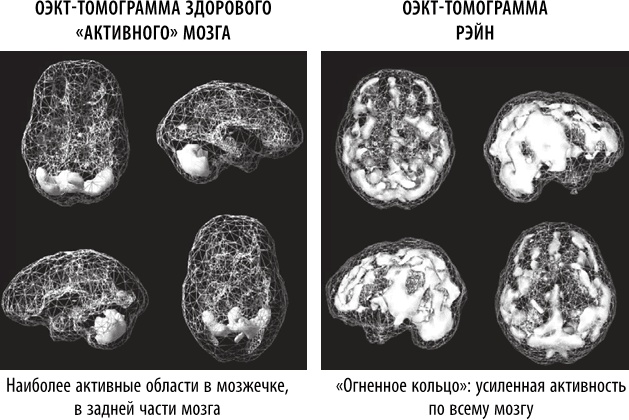

ОЭКТ-томограмма Рэйн выявила сильную аномалию. У нее был так называемый «паттерн огненного кольца», который характеризуется чрезмерной активностью всего мозга, особенно в области передней поясной извилины. Это означало, что она зацикливается на негативных мыслях и поступках. Было легко называть ее плохой девочкой, пока мы не увидели, в каком состоянии находился ее мозг. Мозг ребенка был постоянно перенапряжен, оставляя ей слишком мало возможностей для контроля над своим поведением. Мы назначили Рэйн специальные добавки, чтобы успокоить ее мозг, организовали ей посещение нейротерапевта и изменили ее рацион, исключив глютен и молочные продукты.

Иллюстрация к книге — Полюби свой мозг [i_007.jpg]